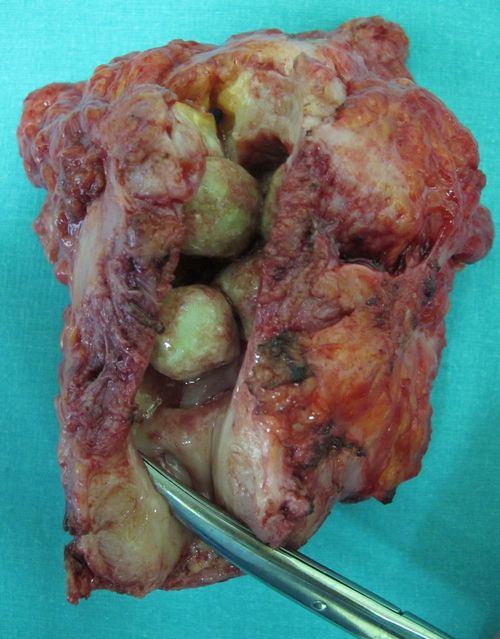

Лучевой цистит с исходом в микроцистис (цистпростатэктомия)